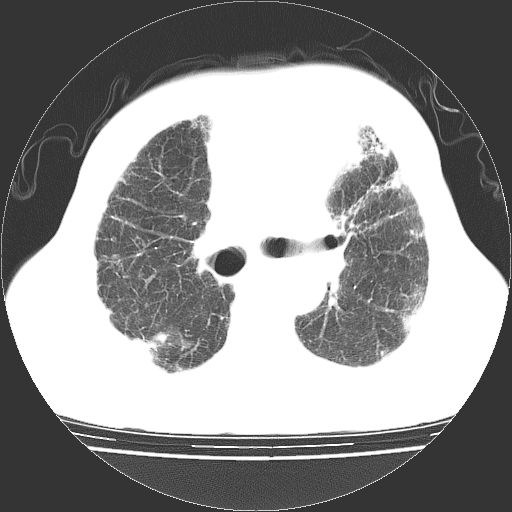

标题: CT25149:男,69岁,反复咳嗽、咳痰五年余,呼吸困难三天。 [打印本页]

男,69岁,反复咳嗽、咳痰五年余,呼吸困难三天。

慢支伴感染、肺气肿、肺心病!支持!另:间质纤维化!

考虑慢性间质性肺炎并肺间质纤维化。

慢支伴感染、肺气肿、肺心病。双肺间质性改变(间质纤维化)。